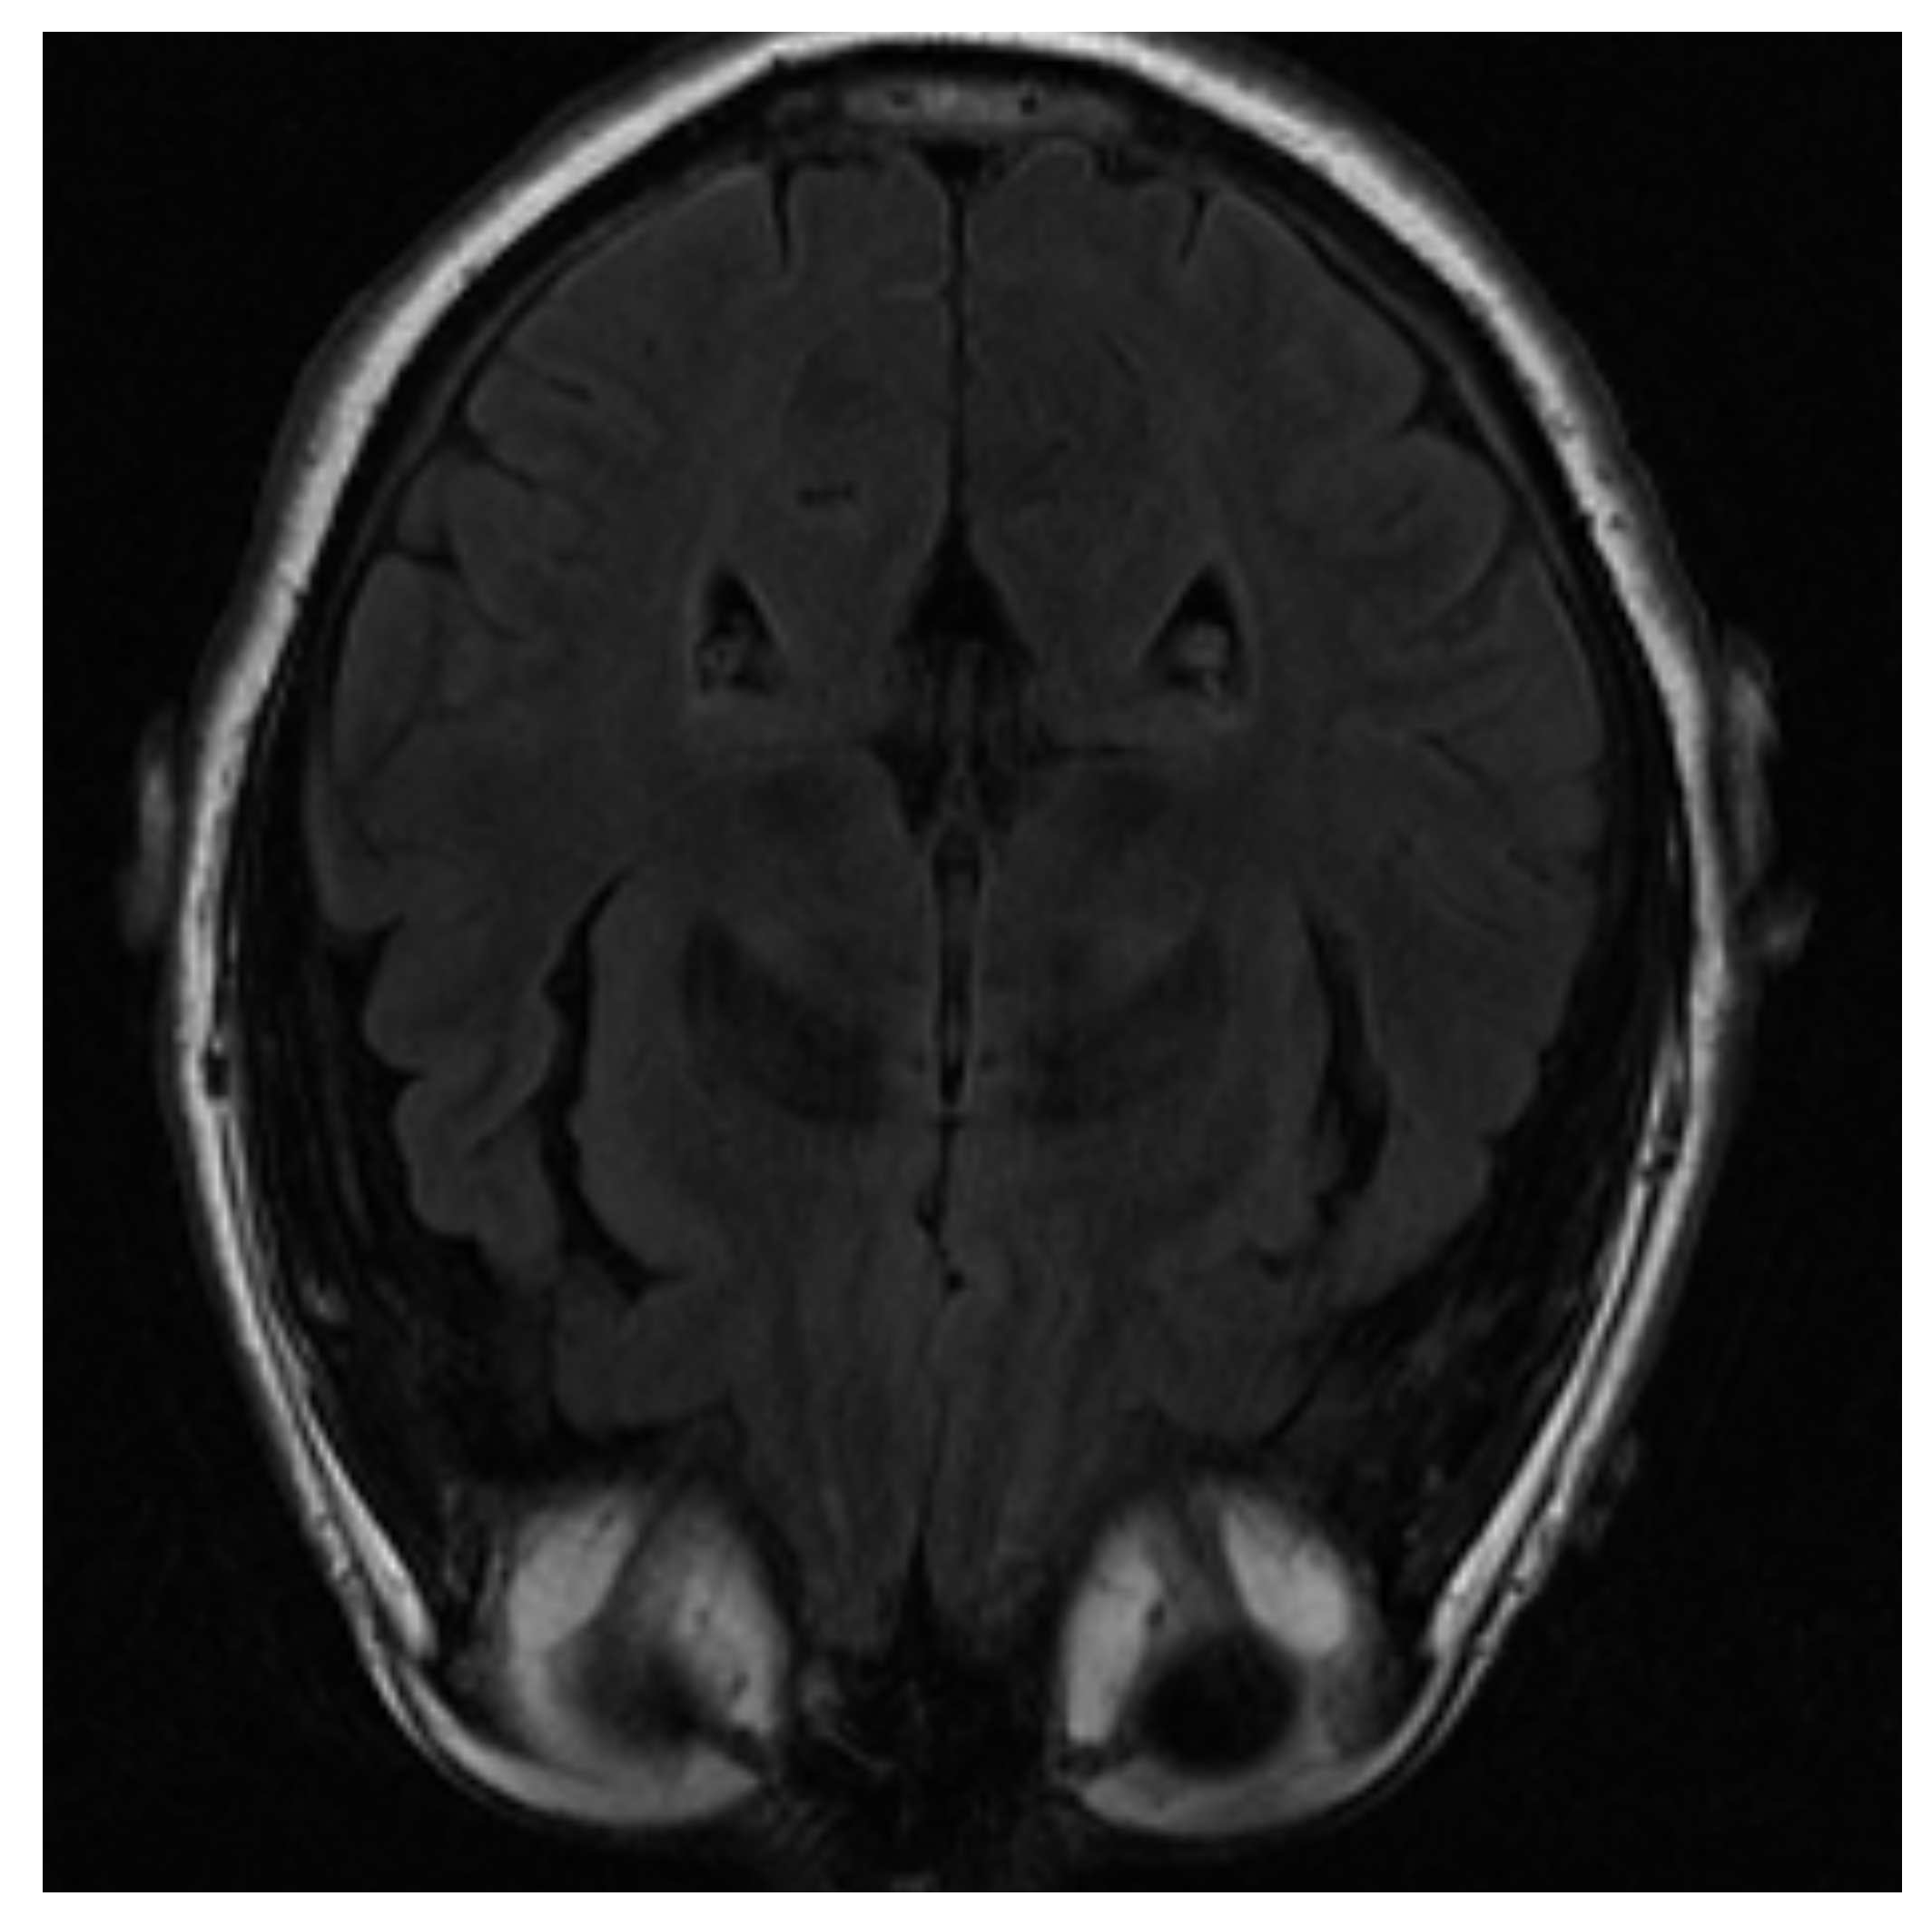

One of the images used in the simulations is shown in Figure 3 and corresponds to an axial slice of the brain in the plane marked by the blue lines in Figure 4. In it, the orbit of the eyes can be distinguished at the bottom. Fat appears with a very intense signal, while water and cerebrospinal fluid have a very low intensity.

The image is blurred in the left orbit, which is an example of an artifact. An artifact is a distortion in the image that has no relation to the subject of the region of the studied body. In this case, it has been generated due to the patient’s movement [28].

Figure 3. MRI image of an axial slice of the brain. In the area below are the eye orbits [27].